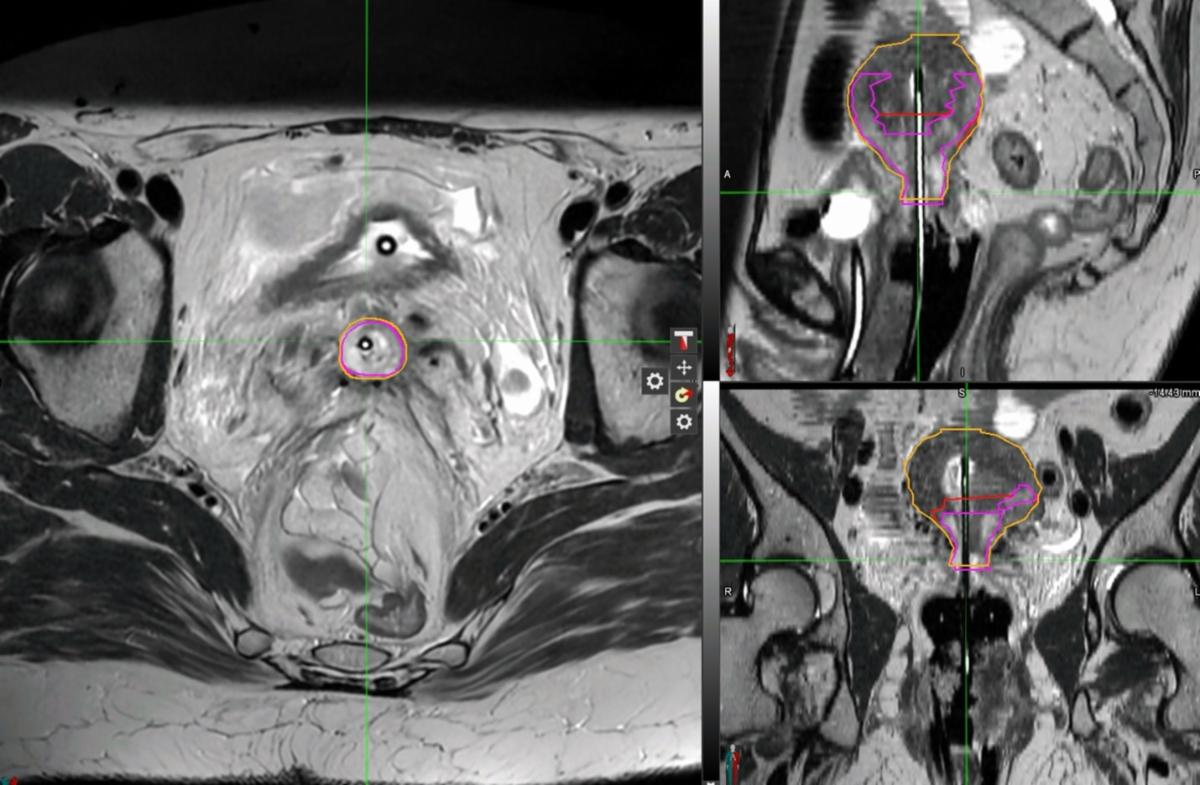

At the time of first brachytherapy, exam under anesthesia demonstrated an irregular cervix without gross exophytic disease. After sounding to 7 cm, a 15-degree MRI/CT-compatible uterine tandem (Elekta, Geneva) was placed under ultrasound guidance with 25 mm semilunar ovoids/colpostats were selected. In anticipating needing to cover disease beyond tandem and ovoids, six interstitial catheters were pre-loaded into the guide tubes which were then attached to the appropriate positions in the ovoids. The ovoids/colpostats/guide tubes/interstitial catheters were advanced into the vaginal fornices, and the colopostats were secured to the tandem to achieve appropriate geometry. A rectal paddle was placed under the ovoids. A locking mechanism was placed. Patient was then imaged with CT in the brachytherapy suite to appropriately advance interstitial catheters in desired positions. Three (2 medial and 1 left lateral posterior) interstitial catheters were advanced 4-5 cm depending on their position. Following confirmation of placement with repeat CT, patient was transferred to MRI scanner where images were obtained, confirming appropriate positioning of the applicators and packing (Figure 3A).

MRI images were then used for brachytherapy planning, and were fused to her CT to assist with catheter reconstruction. The uterus measured approximately 6-6.5 cm left-to-right, with the tandem centered in the uterine cavity (Figures 3B-E). Given this, tandem was likely not going to adequately cover the entirety of residual GTV in the myometrium without excessive hotspots. An individualized plan delivering 7 Gy per fraction was optimized to balance target coverage and normal-tissue sparing, using four channels (tandem x1, ovoids x2, and interstitial needle x1). The rest of the interstitial catheters were not used as they did not improve the plan. Some of the tandem dwell positions were loaded 92 to 130.5 seconds, extending lateral coverage with doses up to 187% of prescription dose (13 Gy). Reasonable coverage was achieved with 91.5% HR-CTV V90% (Table 1).

Figure 3A: HDR-BT Fraction 1 MRI

Figure 3B-E: HDR-BT Fraction 1 MRI in MIM treatment-planning software